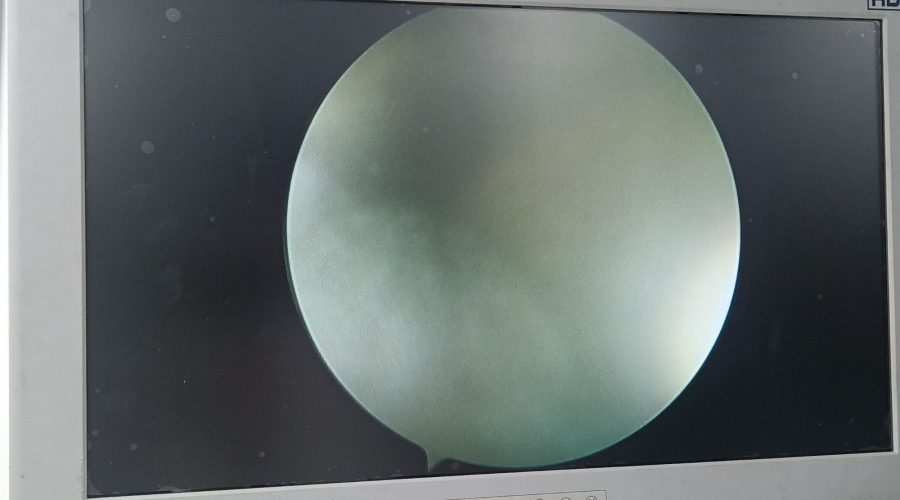

故障內容 | 圖像模糊,物鏡破損 |